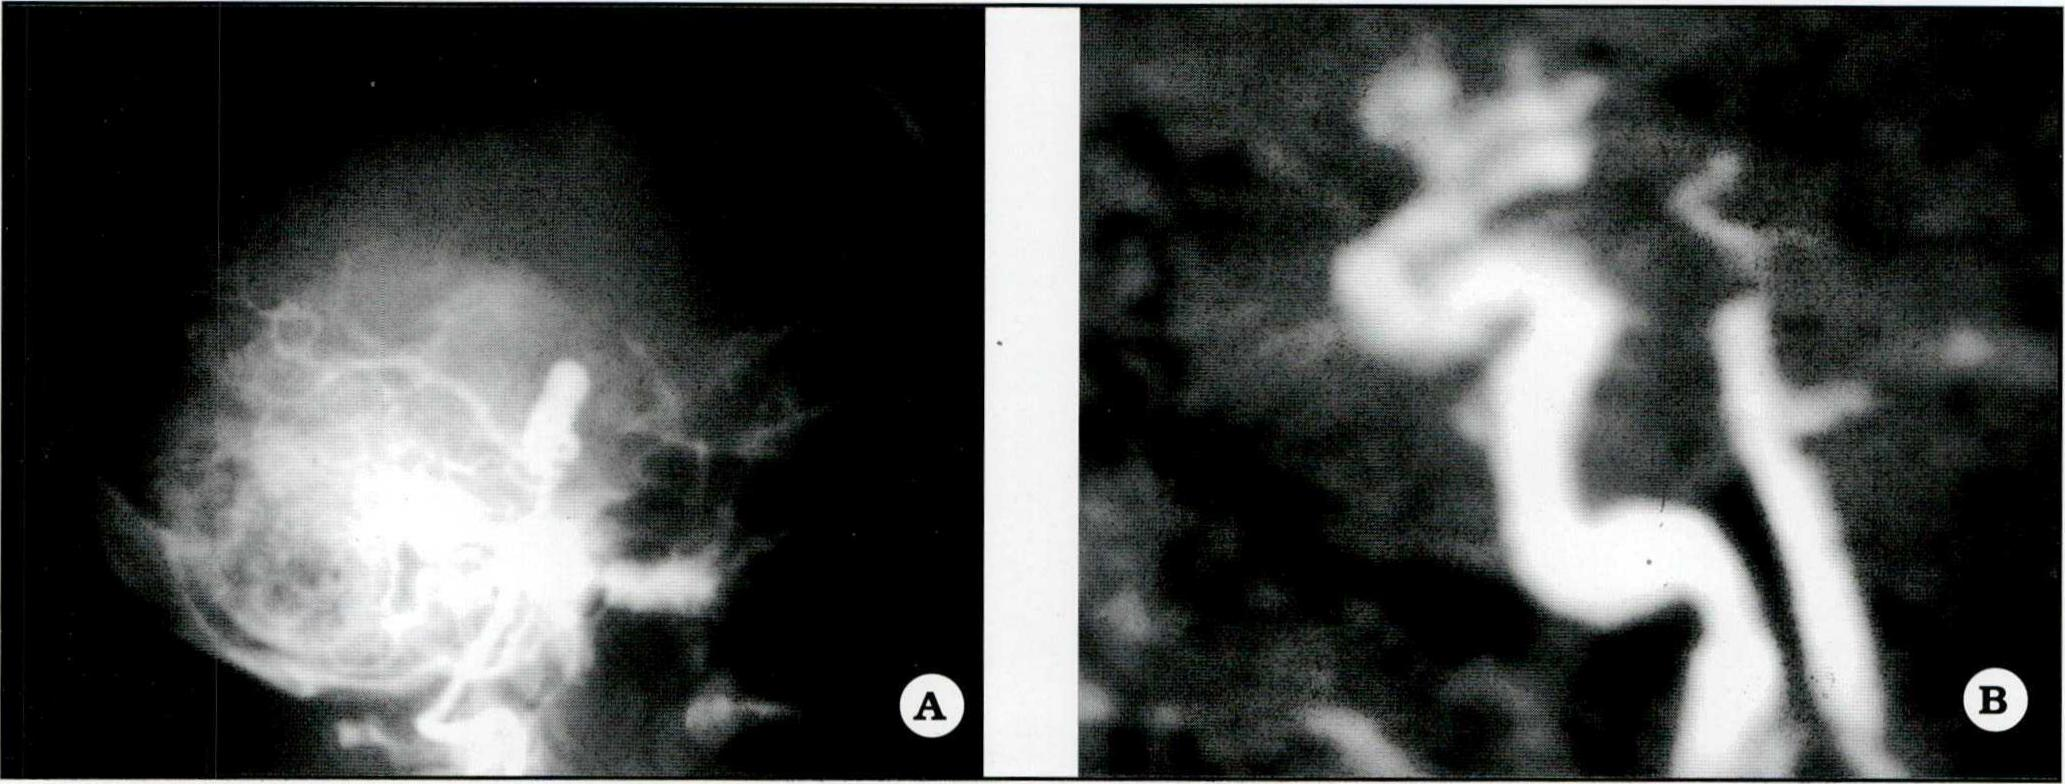

Fig 4. A. Angiograma preoperatorio de un aneurisma del apex de la arteria basilar (proyección perfil). B. Angiorresonancia de control postoperatorio correspondiente al aneurisma basilar, con exclusión del mismo por clipado.